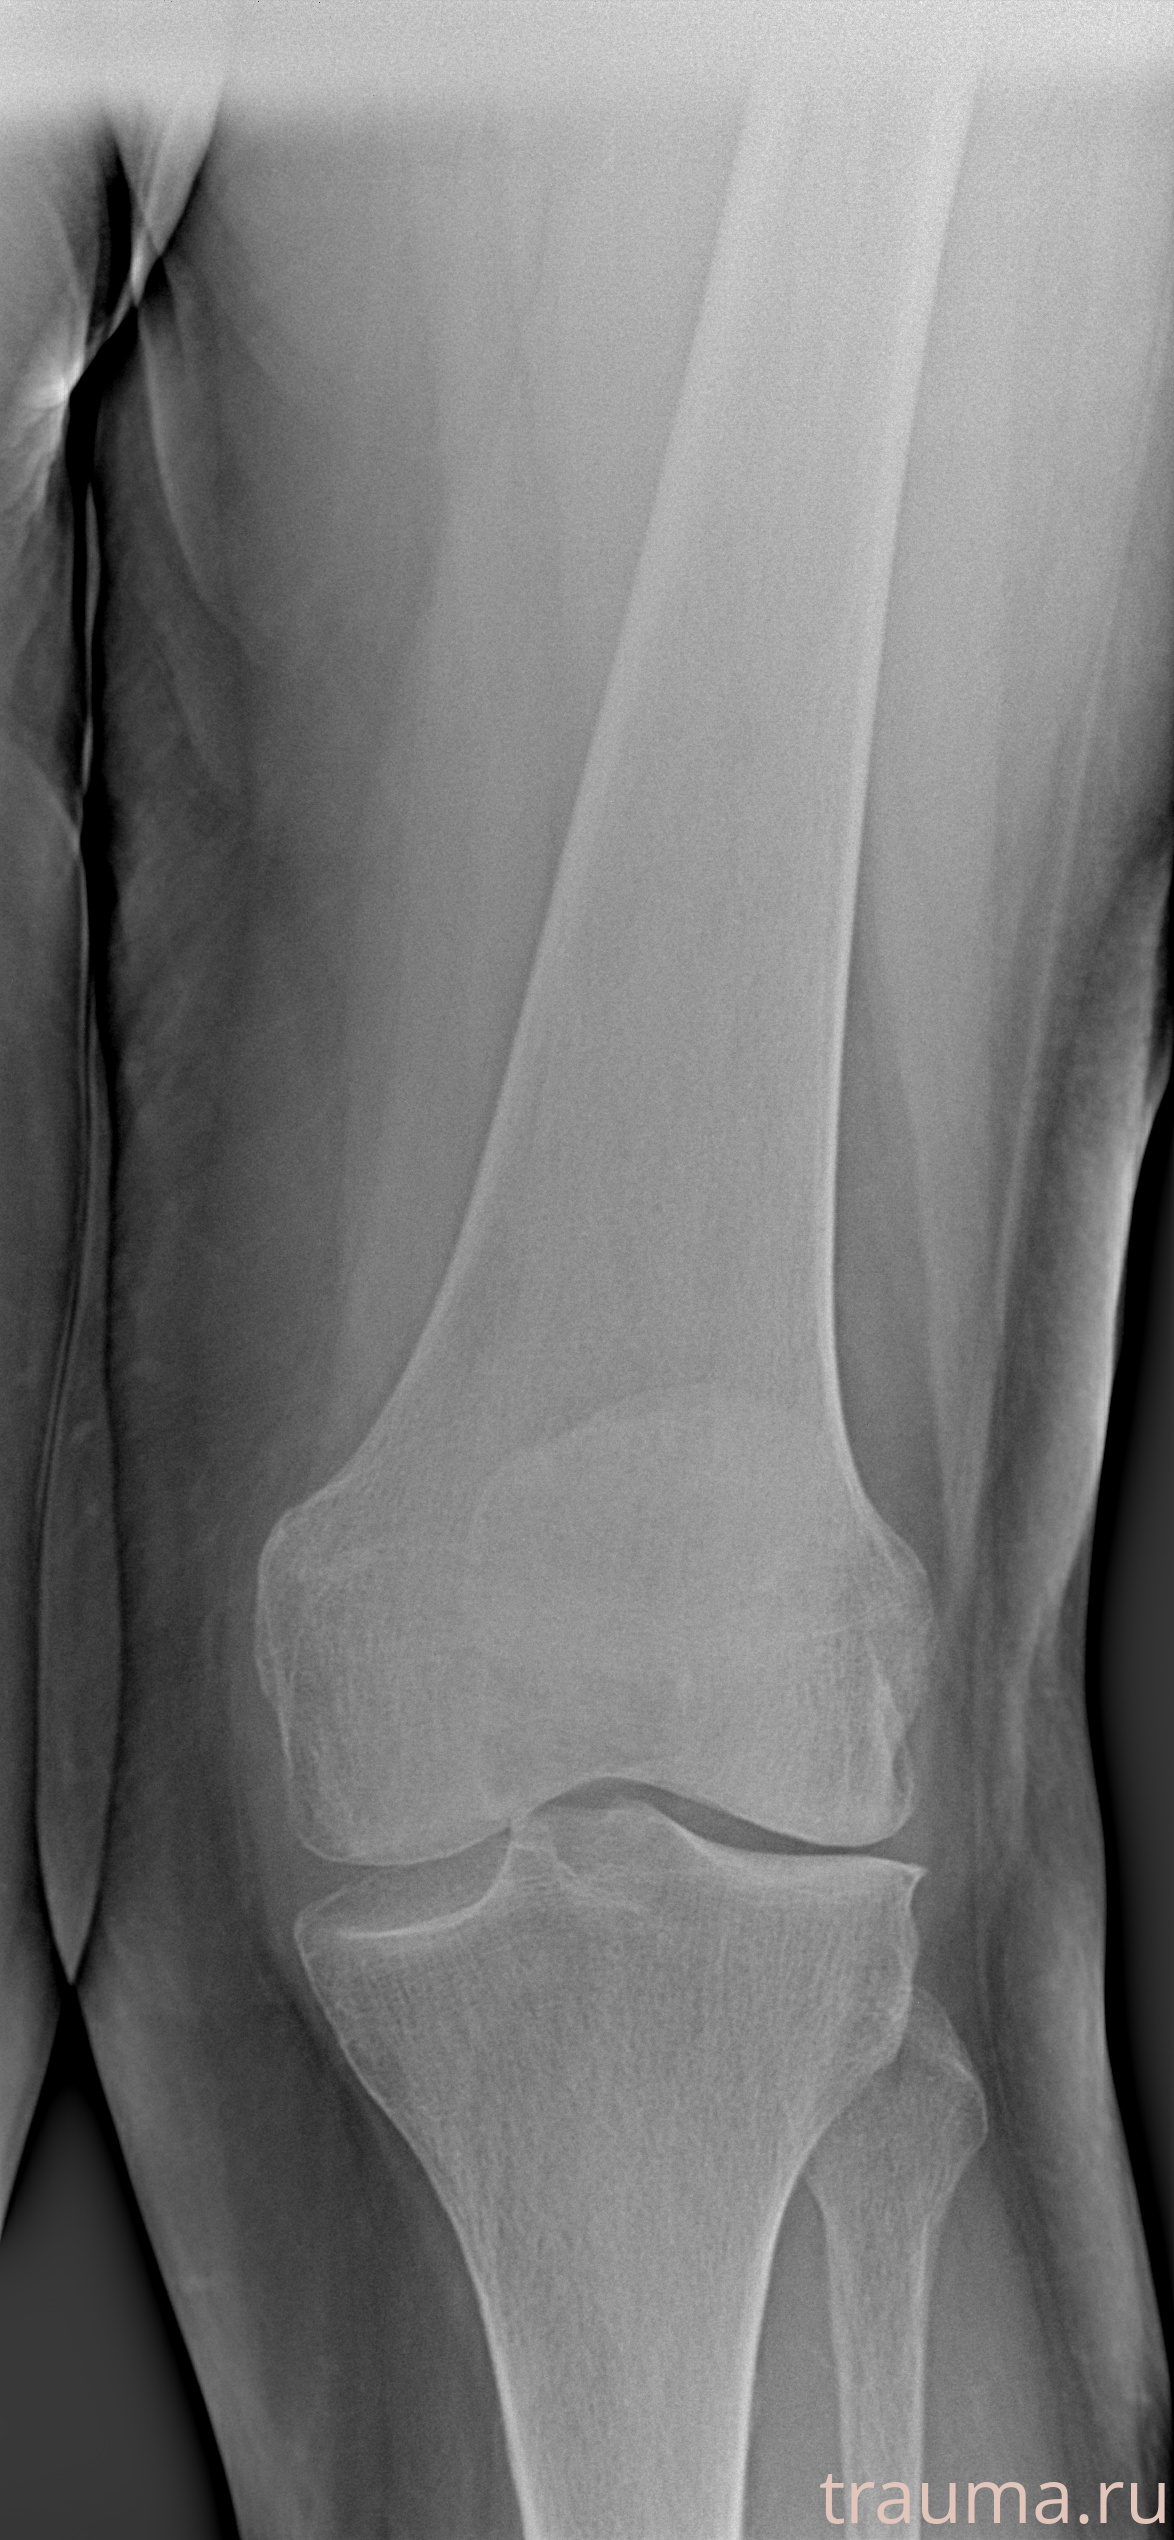

Рентген на дому: по вашему адресу приезжает врач-рентгенолог, травматолог-ортопед с мобильным рентгеновским аппаратом, проводит диагностику травмы или заболевания, делает необходимые рентгенограммы, дает рекомендации по дальнейшему лечению. Получить качественные снимки в домашних условиях возможно благодаря уникальной методике, разработанной МосРентген Центром для института  Склифосовского